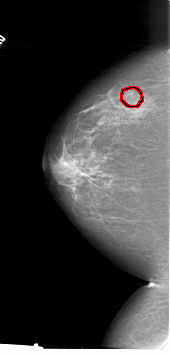

A_1415_1.LEFT_CC

LEFT_CC LINES 6766 PIXELS_PER_LINE 3226 BITS_PER_PIXEL 12 RESOLUTION 43.5 OVERLAY

FILE: A_1415_1.LEFT_CC.OVERLAY

TOTAL_ABNORMALITIES 1

ABNORMALITY 1

LESION_TYPE CALCIFICATION TYPE PLEOMORPHIC DISTRIBUTION CLUSTERED

ASSESSMENT 4

SUBTLETY 3

PATHOLOGY MALIGNANT

TOTAL_OUTLINES 1

BOUNDARY